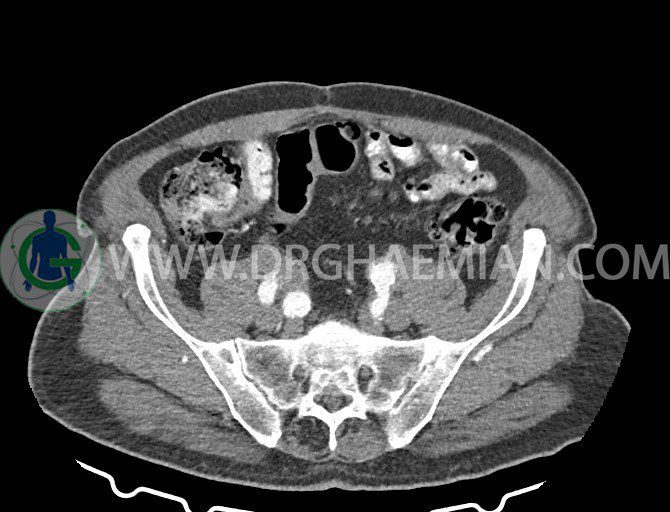

سی تی اسکن لگن یکی از روش های تصویربرداری با سی تی اسکن است. این روش با استفاده از تشعشعات تصاویر عرضی از ناحیه شکمی ایجاد میکند. در این کیس ديورتيكولوزيس، کیست های کورتیکال در هر دو کلیه، لنفادنوپاتی، کلسیفیکاسیون دیواره آئورت و شریان ایلیاک، تغییرات DJD ناحیه توراکولومبار و پروستات بزرگتر از عادی دیده می شود.

– کلسيفيکاسيون ديواره آئورت و شريان ها ايلياک همراه با نشانه هاي ترومبوز مورال در بيفورکاسيون ائورت با امتداد به پروگزيمال هاي شريان هاي ايلياک

– پروستات به ابعاد mm 45 x 54، بزرگ تر از نرمال